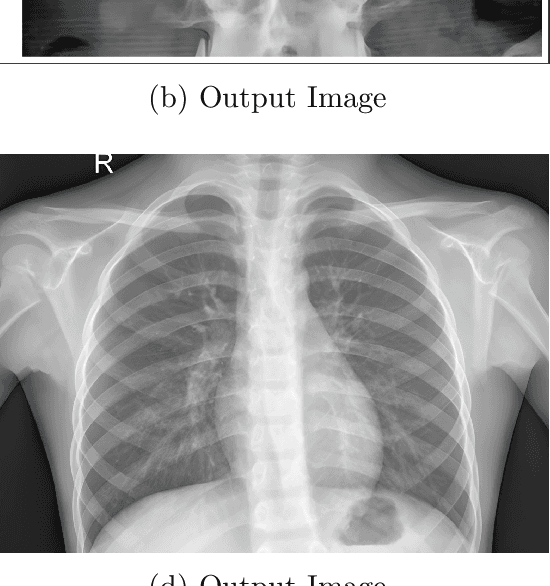

Abstract:While X-ray imaging is indispensable in medical diagnostics, it inherently carries with it those noises and limitations on resolution that mask the details necessary for diagnosis. B/W X-ray images require a careful balance between noise suppression and high-detail preservation to ensure clarity in soft-tissue structures and bone edges. While traditional methods, such as CNNs and early super-resolution models like ESRGAN, have enhanced image resolution, they often perform poorly regarding high-frequency detail preservation and noise control for B/W imaging. We are going to present one efficient approach that improves the quality of an image with the optimization of network transmission in the following paper. The pre-processing of X-ray images into low-resolution files by Real-ESRGAN, a version of ESRGAN elucidated and improved, helps reduce the server load and transmission bandwidth. Lower-resolution images are upscaled at the receiving end using Real-ESRGAN, fine-tuned for real-world image degradation. The model integrates Residual-in-Residual Dense Blocks with perceptual and adversarial loss functions for high-quality upscaled images with low noise. We further fine-tune Real-ESRGAN by adapting it to the specific B/W noise and contrast characteristics. This suppresses noise artifacts without compromising detail. The comparative evaluation conducted shows that our approach achieves superior noise reduction and detail clarity compared to state-of-the-art CNN-based and ESRGAN models, apart from reducing network bandwidth requirements. These benefits are confirmed both by quantitative metrics, including Peak Signal-to-Noise Ratio and Structural Similarity Index, and by qualitative assessments, which indicate the potential of Real-ESRGAN for diagnostic-quality X-ray imaging and for efficient medical data transmission.